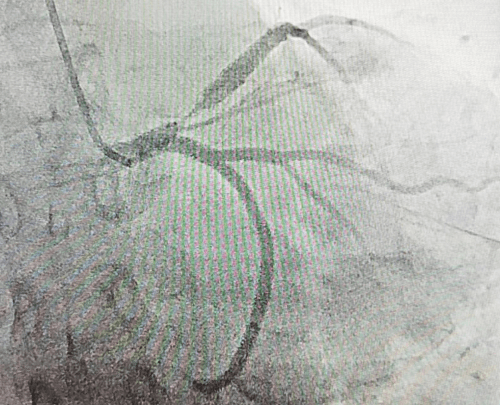

子宮動脈栓塞術屬于血管介入性治療,方法是于股動脈穿刺進針插入導管,在X射線造影下定位進入兩側子宮動脈,注入栓塞劑完全栓塞子宮動脈,從而達到止血或讓子宮肌瘤和病灶缺血壞死的目的;2022年12月6日,在崔旭輝主任、孟慶槐副主任醫(yī)師、馬力主治醫(yī)師等我院介入團隊協(xié)作下,成功為患者進行了雙側子宮動脈栓塞術,術后患者子宮異常出血停止,效果立竿見影,患者病情恢復良好。

左側子宮動脈栓塞前后對照